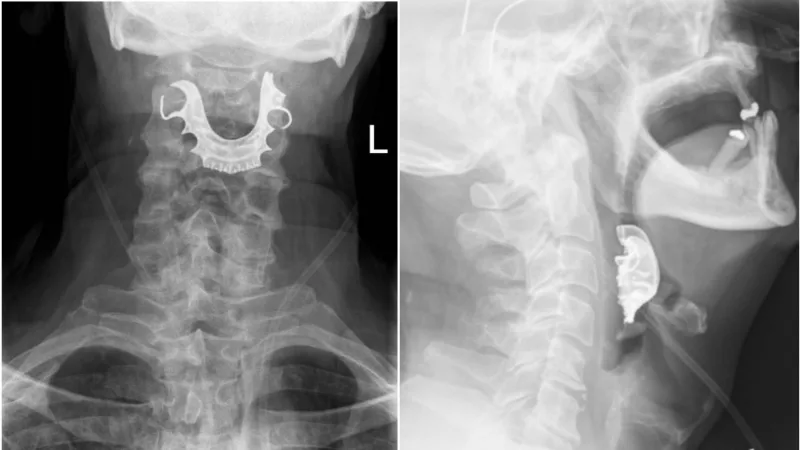

बता दें कि जांच में नाक के जरिए फाइबर ऑप्टिक कैमरा अंदर डाला जाता है। कैमरे में दिखा गले में एक बड़ी सी चीज फंसी हुई है। जांच में गले में नकली दांत फंसे होने की बात पता चली। सर्जरी करने के बाद उनके नकली दांत निकाले गए और 6 दिन बाद उनको डिस्चार्ज कर दिया गया। जैक का कहना है उन्हें सांस लेने में भी परेशानी आ रही थी। लेटने के दौरान सांस नहीं ले पाते थे। जैक के साथ जो हुआ उससे उन सभी को सतर्क रहने की ज़रुरत है जो नकली दांत लेकर ऑपरेशन कराते हैं।